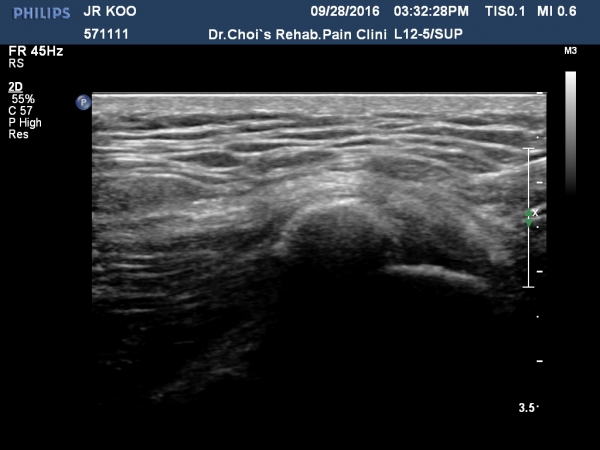

´ëÀüÀÚ Á¾´Ü¸é°Ë»ç¿¡¼­ ¼ÒµÐ±Ù¿¡ ¼®È¸È­À½¿µÀÌ °üÂûµÊ(»çÁø 3, 4).